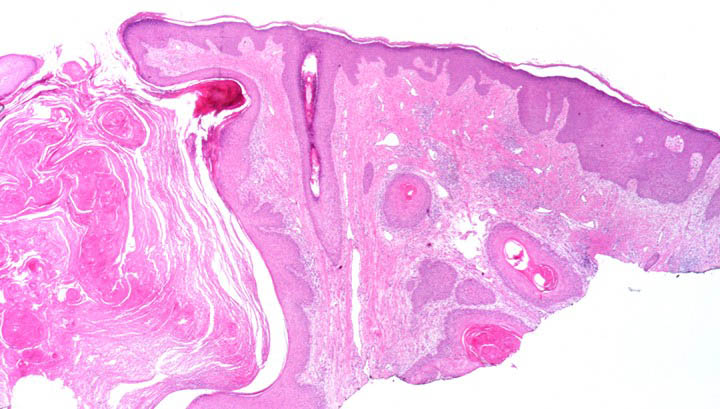

Squamous Cell Carcinoma = الكارسينوما شائكة الخلايا